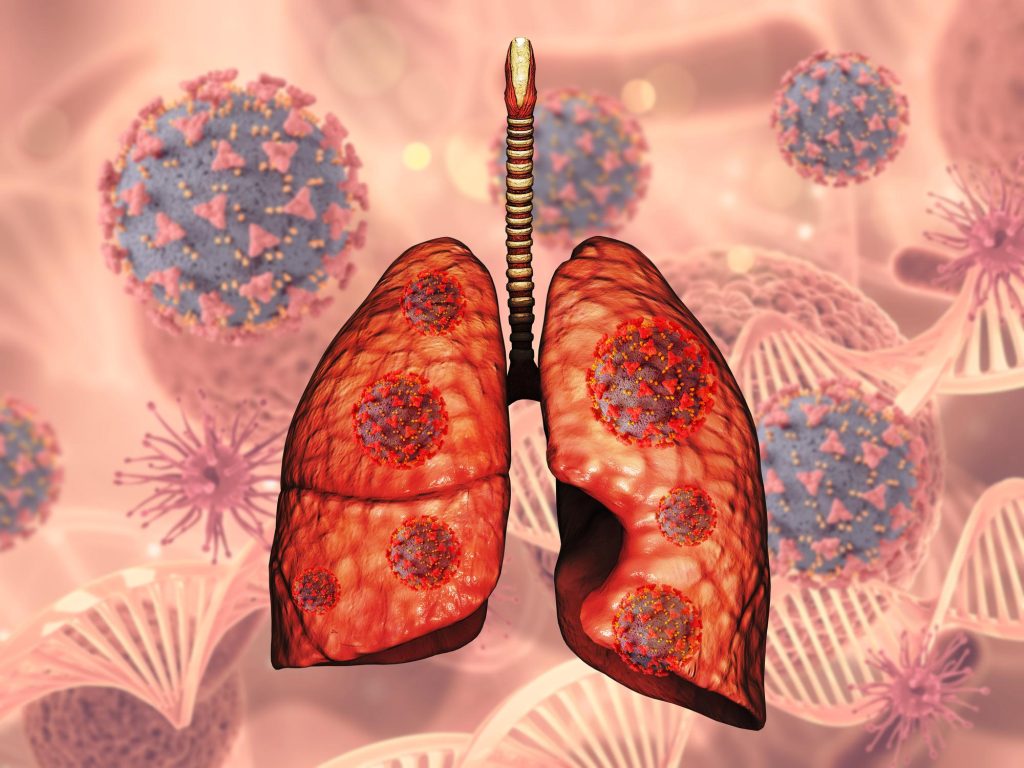

Lung cancer is one of the most common types of thoracic cancer and begins in the lungs.

1. About Lung Cancer

Types of Lung Cancer